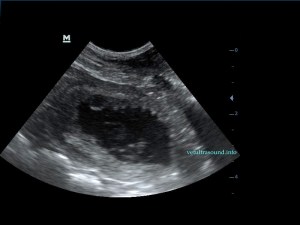

Η πάχυνση του τοιχώματος και η δοκίδωση του βλεννογόνου είναι εμφανής σε όλες τις εικόνες. Πολλές φορές οι λαγόνιοι λεμφαδένες μπορεί να είναι ήπια διογκωμένοι και να έχουν αντιδραστική ηχομορφολογία. Ο έλεγχος με έγχρωμο Doppler του τοιχώματος της άδειας κύστης μπορεί να μας δείξει ροή αίματος στα αγγεία της κύστης. Αντίθετα, είναι πιθανό, όσο η κύστη γεμίζει με ούρο η ροή αίματος να μην είναι ορατή με το Doppler. Αυτό συμβαίνει συχνά στη χρόνια βακτηριακή κυστίτιδα λόγω της ίνωσης του τοιχώματος της ουροδόχου και αυτή είναι μία από τις αιτίες της μη ανταπόκρισης στη θεραπεία. Η συγκεκριμένη παθοφυσιολογία έχει μελετηθεί στον άνθρωπο με την βοήθεια ενδοσκοπικού υπερήχου.

The increase of thickness of the urinary bladder wall and the striation of the mucosa is evident. Inguinal lymphnodes are usually prominent and mildly enlarged. Colour Doppler may reveal the blood flow of the mucosa of the empty urinary bladder, whereas the blood flow in a full bladder appears decreased. This could be because of the fibrosis of the urinary bladder wall and could explain why sometimes chronic conditions like these do not respond well to antibiotics. This pathophysiology has been studied in humans with the use of endoscopic ultrasound.